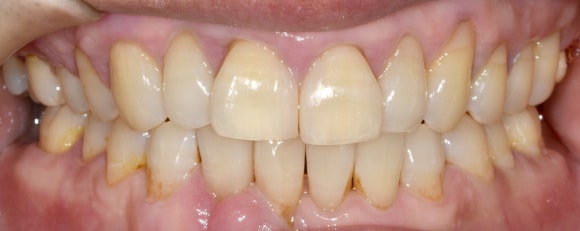

위와 같이 치료가 완료되었습니다. 제가 처음에 계획했던 것보다 훨씬 심미적으로 치료가 잘 되어 기분이 좋았네요.

위아래 앞니의 치아의 축이 잘 맞게 되었습니다. 교정을 하지 않았는데 마치 교정을 한 것처럼 되었네요.

앞니 벌어짐도 해결하고 치열도 고르게 하는 일석이조의 치료였습니다.

비교 사진 보시면 더욱 직관적으로 전후 차이를 느끼실 겁니다.

앞니 벌어짐을 해소하려 왔다가 가지런한 앞니까지 얻게 되신 케이스였네요.^^